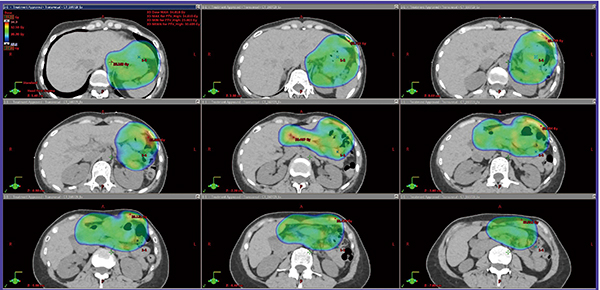

●症例3:胃原発の辺縁帯B細胞性リンパ腫MALT型 stageⅠ

RapidArcを用いて30.6 Gy/17回のISRTを行った。呼吸移動対策として,バリアンメディカルシステムズ社の「リアルタイム ポジショニング マネジメント システム」でモニターしたcone beam CTによるIGRTを行った。急性毒性として,軽微な食欲不振を認めたのみであった。経過観察中の肝機能・腎機能は軽微な上昇にとどまった。完全寛解を2年間維持している。線量分布図を図3に示す。

図3 症例3:胃原発の辺縁帯B細胞性リンパ腫MALT型 stageⅠに対するRapidArcを用いたISRTの例